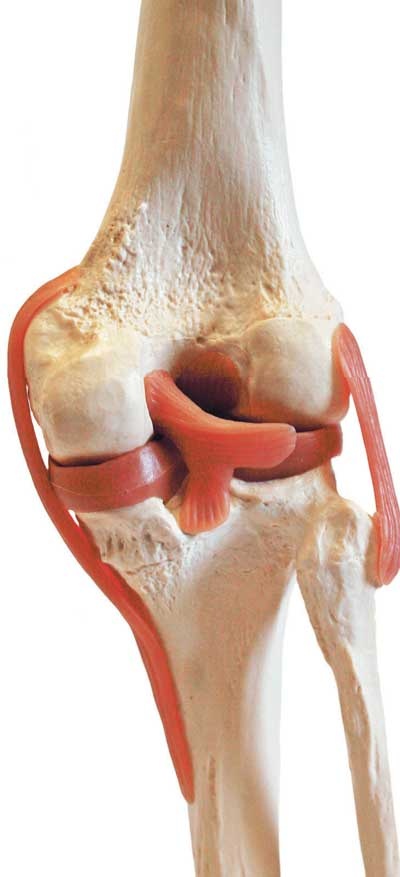

Сустав – самая распространенная и сложная форма соединения костей. Обязательными элементами любого сустава, независимо от места расположения и степени подвижности, являются суставные поверхности, суставная сумка и суставная полость.

Соединение костей в коленном суставе (вверху – рентген, внизу – модель)

Суставные поверхности костей, образующие сустав, плотно прилегают друг к другу. Они покрыты особым гиалиновым хрящом, чья гладкая поверхность и эластичность облегчают движение в суставе, смягчают испытываемые им толчки и сотрясения.

Суставные поверхности костей окружает суставная капсула – оболочка из соединительной ткани. Обычно она крепится к костям в месте перехода суставной поверхности в надкостницу и прочно с ней срастается. Снаружи капсула укреплена связками, которые располагаются в местах наибольшей нагрузки.

Суставные поверхности и капсула ограничивают собой небольшое герметично закрытое пространство – полость сустава, заполненную малым количеством вязкой синовиальной жидкости, роль которой заключается в уменьшении трения в суставах при движении. Благодаря отрицательному давлению в суставной полости поверхности костей тесно прилегают друг к другу.